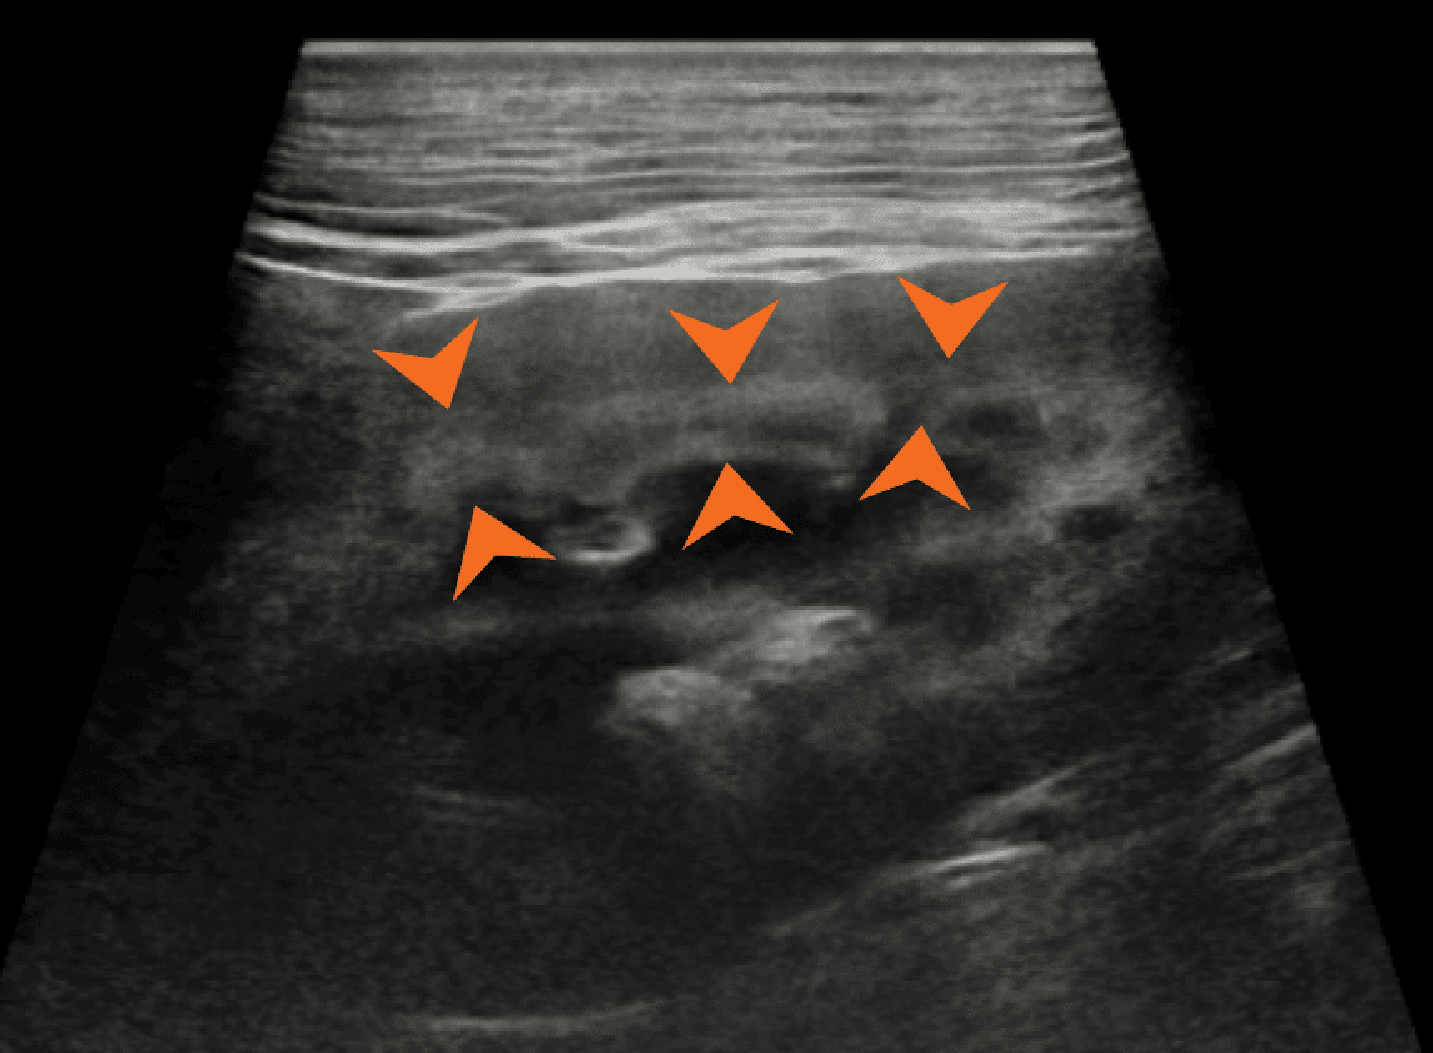

Ryc. 5. Badanie ultrasonograficzne metodą dopplera mocy lewej nerki kota, ukazujące równomiernie nieregularne brzegi w miejscach, gdzie naczynia nerkowe przebiegają wzdłuż torebki nerki (groty strzałek).

Prawidłowy obraz ultrasonograficzny nerek został szczegółowo omówiony w innych źródłach,7 a poniższy artykuł koncentruje się na przewlekłej chorobie nerek u kotów i psów. Nerki powinny być obrazowane w trzech projekcjach – strzałkowej, dogrzbietowej i poprzecznej (ryc. 1).7 U psów, zwłaszcza małych ras, opisano obecność hiperechogenicznego zewnętrznego pasma rdzeniowego, które obserwuje się z umiarkowaną częstością u pacjentów bez stwierdzonej choroby nerek (ryc. 2).8 U kotów kora nerek może być jednorodnie silnie hiperechogeniczna ze zwiększonym w następstwie zróżnicowaniem korowo-rdzeniowym wtórnym do lipidozy kanalików bliższych (ryc. 3).9 Odkładanie się tłuszczu w kanalikach nerkowych jest konsekwencją otyłości bez jednoczesnego upośledzenia czynności nerek.10 Dodatkowo rutynowo obserwuje się zależny od kąta badania artefaktowy wzrost hiperechogeniczności kory i rdzenia nerek, wtórny do anizotropii, w obszarach, w których kanaliki nerkowe ułożone są prostopadle do płaszczyzny fali ultradźwiękowej. Na przykład podczas obrazowania nerki w projekcji strzałkowej echogeniczność biegunów doczaszkowego i doogonowego będzie ogniskowo i artefaktowo zwiększona (ryc. 4).11 Z doświadczenia autorów wynika, że łagodna nieregularność brzegów nerek, szczególnie u kotów, może być obserwowana w miejscach, gdzie naczynia nerkowe przebiegają wzdłuż torebki nerkowej, i nie powinna być błędnie interpretowana jako zmiana zwyrodnieniowa (ryc. 5). W lokalizowaniu tych naczyń użyteczna jest ultrasonografia dopplerowska kodowana kolorem lub w trybie mocy.